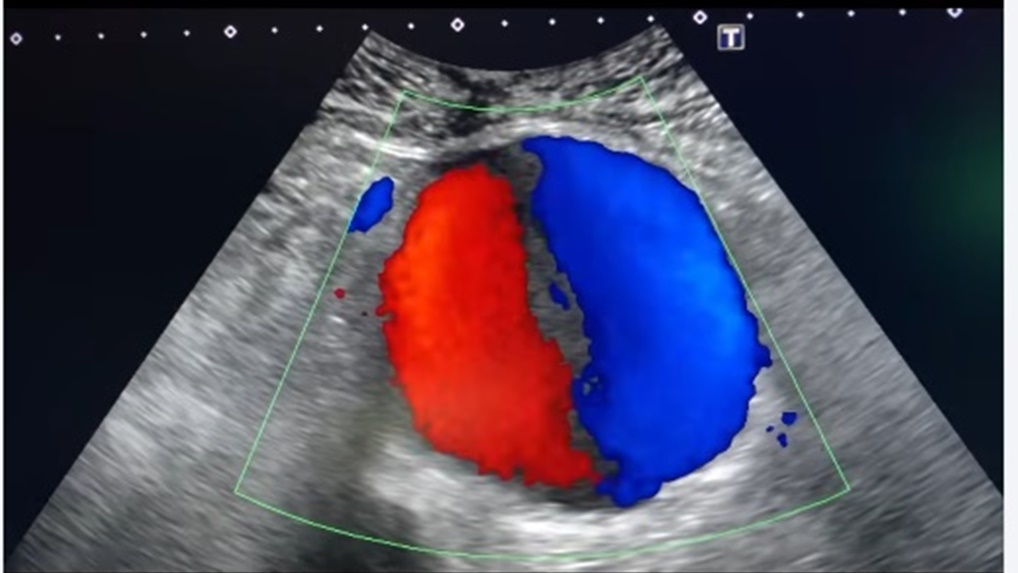

彩色杜卜勒超音波偵測揪出腹主動脈瘤

錢政弘進一步打開彩色杜卜勒超音波偵測,發現水泡內有血液流動,呈現太極圖形,確定是一個腹部主動脈瘤,且直徑高達9公分。一般而言,腹部主動脈瘤超過5.5公分就有高度破裂風險,像阿公這樣9公分大的動脈瘤,破裂風險超過50%,幾乎隨時會破裂,而破裂會引起致命的大量內出血,即使在醫院內,死亡率也高達70%。